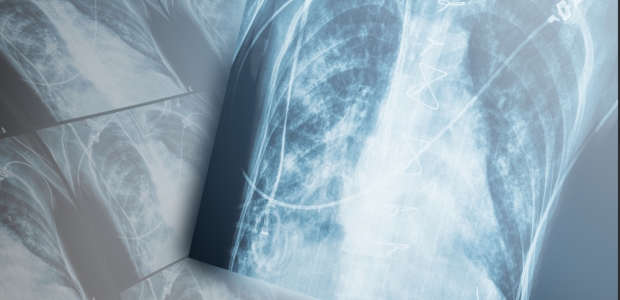

"Given the increase in occupational cancer incidents in the fire service, we feel it is best to err on the side of caution as we await additional scientific research on PPE and learn more about the absorption of carcinogens near the forehead, jaw, neck, and throat," said Ed Conlin, the NFPA Public Fire Protection division's manager.